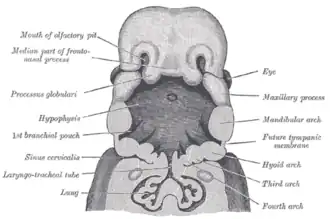

From the third to the eighth week the face and neck develop.

Representing different stages of embryogenesis

Head and neck at 32 days

Head and neck at 32 days